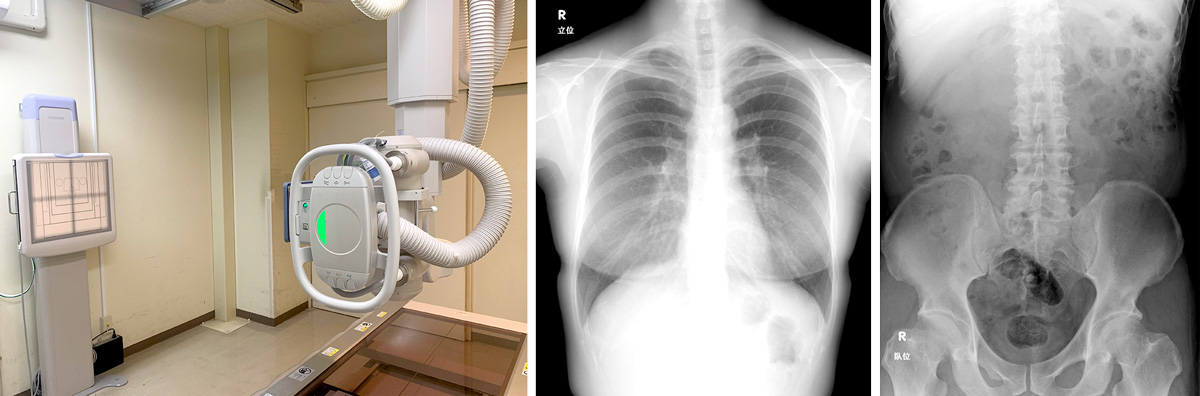

X線撮影室:MRAD-A50S RADREX (Canon)

X線撮影室では、レントゲンの検査を行っています。レントゲンとはX線という放射線を使うことで、体の中を写すカメラのようなものです。

全身の臓器、骨などの検査を行います。